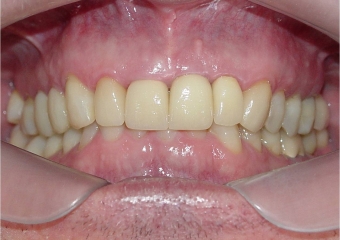

Mordida inicial